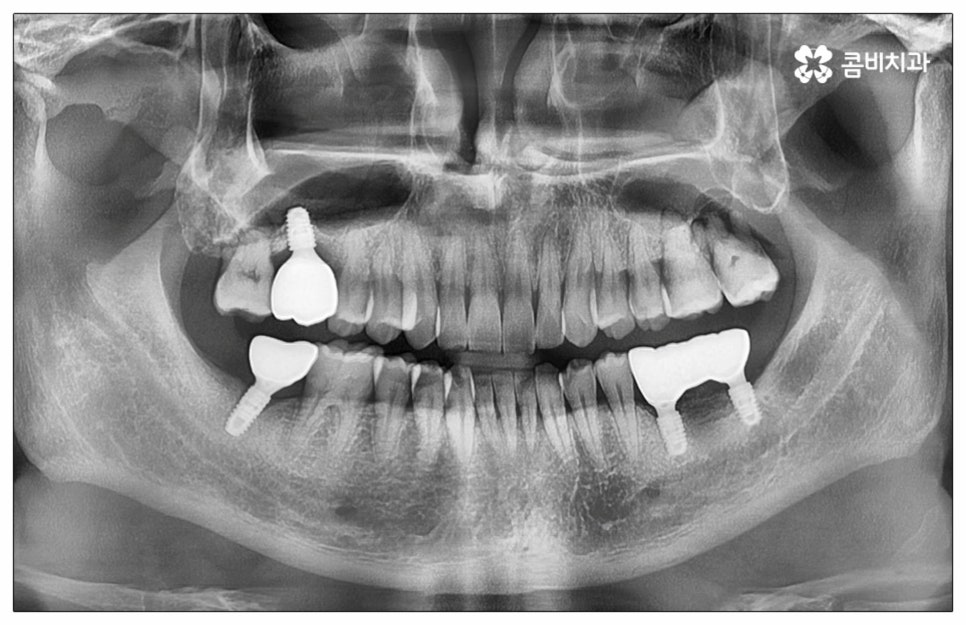

예전에는 이런 상황에서 틀니를 많이 이용하였으나 저작력 회복이 본래 자신의 치아 대비 20~30% 정도 밖에 되지 않고 잦은 탈락 위험 및 이물감, 잇몸을 눌러 장기적으로 잇몸뼈가 내려앉을 수 있다는 점 등 여러 가지 불편함이 있어 요즘은 임플란트 시술을 선호하시는 분들이 더 많아지고 있어요. 임플란트란 인체에 무해하며 잇몸뼈와 잘 결합하는 인공 치근을 잇몸뼈에 직접 식립하고 그 위로 기둥이 되는 중간 지대주와 치아 머리가 되는 크라운 보철물을 연결하여 인공 치아를 만들어 주는 시술을 말하는데, 자연 치아의 80% 정도 저작력 회복이 가능하기 때문에 식사를 할 때 음식을 크게 가리지 않아도 된다는 점 그리고 심미적으로 봤을 때 주변 치아와 자연스럽게 어우러진다는 점 때문에 각광을 받고 있습니다. 게다가 건강 보험 가입자이면서 만 65세 이상 부분 무치악 환자라면 평생 임플란트 2개까지 보험 적용을 받아 비용 부담을 줄일 수 있기 때문에 더욱 더 수요가 늘어나 이제는 치아 상실에 대체하는 대표적인 방법으로 임플란트 시술이 꼽히고 있는데요.

많이 대중화 되었다고 해도 임플란트 수술 자체가 술자의 숙련도에 크게 영향을 받는 복잡하고 고난도의 진료인 것은 틀림이 없기 때문에 담당 의료진이 해당 분야 임상 경험이 풍부한지, 뛰어난 기술력과 노하우를 가지고 있는지 꼼꼼하게 체크해 보실 필요가 있어요. 특히 노년층의 경우 당뇨, 고혈압 등 만성 질환을 앓고 있는 경우가 많아 혹시 상시 복용하고 있는 약이 있는지, 현재 환자 개개인의 상태는 어떤지, 사전 처치가 필요한 부분은 없는지 등등 수술 조건을 좀 더 까다롭게 평가한 후 환자분들과 이에 대해 충분히 상담하고 맞춤형 치료 계획을 세워 진행해야 하며 이를 위해 3D CT 와 같은 디지털 검진 장비를 통해 구강 내부 구조를 면밀하게 살피고 방대한 임상 데이터를 축적한 정품 임플란트 재료를 이용하여 연령이나 회복 정도를 살펴보면서 체력적 부담을 줄이는 방향으로 무리하지 않게 식립하는 것이 무엇보다 중요하다고 할 수 있습니다.

이때 추가 수술은 비급여 항목으로 건강보험임플란트 대상에서 제외되니 이에 대해서도 꼼꼼하게 살펴보시고 정밀 검진 후 담당 의료진과 자신의 상황에 대해서 충분하게 상담해 보시길 권유드리고 있습니다. 추가 수술의 대표적인 예로는 뼈이식 수술이 있는데요. 이것은 임플란트를 식립할 때 바탕이 되는 잇몸뼈의 높이나 폭, 밀도 등이 부족하다면 먼저 이를 보충해 주고 나서 임플란트를 심어주는 과정을 의미하며 같은 이유로 식립 성공률이나 장기적인 안정성을 높이기 위해 꼭 필요한 사전 처치, 즉 상악동 거상술 및 치주 질환 관련 수술 등을 먼저 해야 한다면 이 역시 추가 수술의 범주로 들어가니 자신의 상황에 대해서 상세하게 알아보실 필요가 있어요.